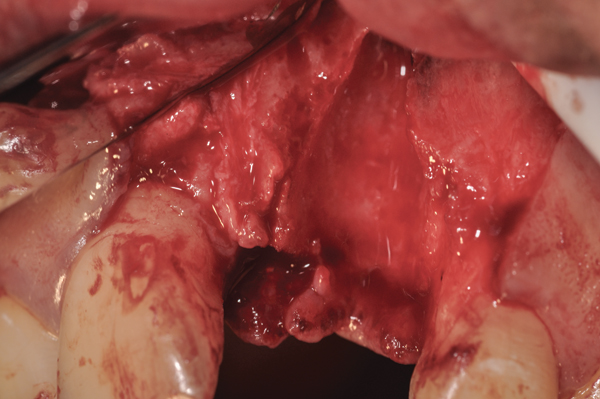

Fig 10. At 3 months postoperative, the flap was elevated, demonstrating a restored buccal plate of bone.

Figure 10

Removal of the d-PTFE at 4 or 4 to 6 weeks does not appear to be detrimental to bone regeneration,7,8,11,23,36 as is shown in the four cases presented (Figure 1 through Figure 25). Conceptually, the osteoid tissue is dense enough to preclude penetration of the epithelium or connective tissue that would inhibit healing. There are several possible explanations as to why barriers can be removed earlier than previously recommended:

The four presented cases shown in Figure 1 through Figure 25 were all treated in a similar manner as outlined in detail in the captions for the first case (Figure 1 through Figure 11). In all four cases, teeth with pathosis were removed, buccal and lingual flaps were elevated, and sites were surgically debrided. A Cytoplast d-PTFE barrier was sized and inserted usually under the buccal flap, the bone graft was added, the barrier was then tucked under the lingual flap, and the flaps were sutured. Bone grafts were used in all of the cases, because buccal bony plates were resorbed and the bone graft helped support the barrier.